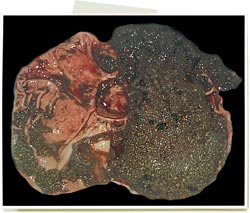

Reins avec des foyers blanchâtres multifocaux

Il s’agit très probablement de néphrite interstitielle. C'est une lésion banale qui est associée à l'infection par le PCV2, mais qui peut avoir d'autres origines.

Ulcère de l'estomac

Pathologie d'origine multifactorielle. Cette lésion est fréquente lors d'atteinte par le PCV2, à cause de l'état d'amaigrissement et donc d’un jeûne prolongé (ce qui favorise l'ulcère de type peptique). Ce n'est pas une lésion provoquée par le PCV2.